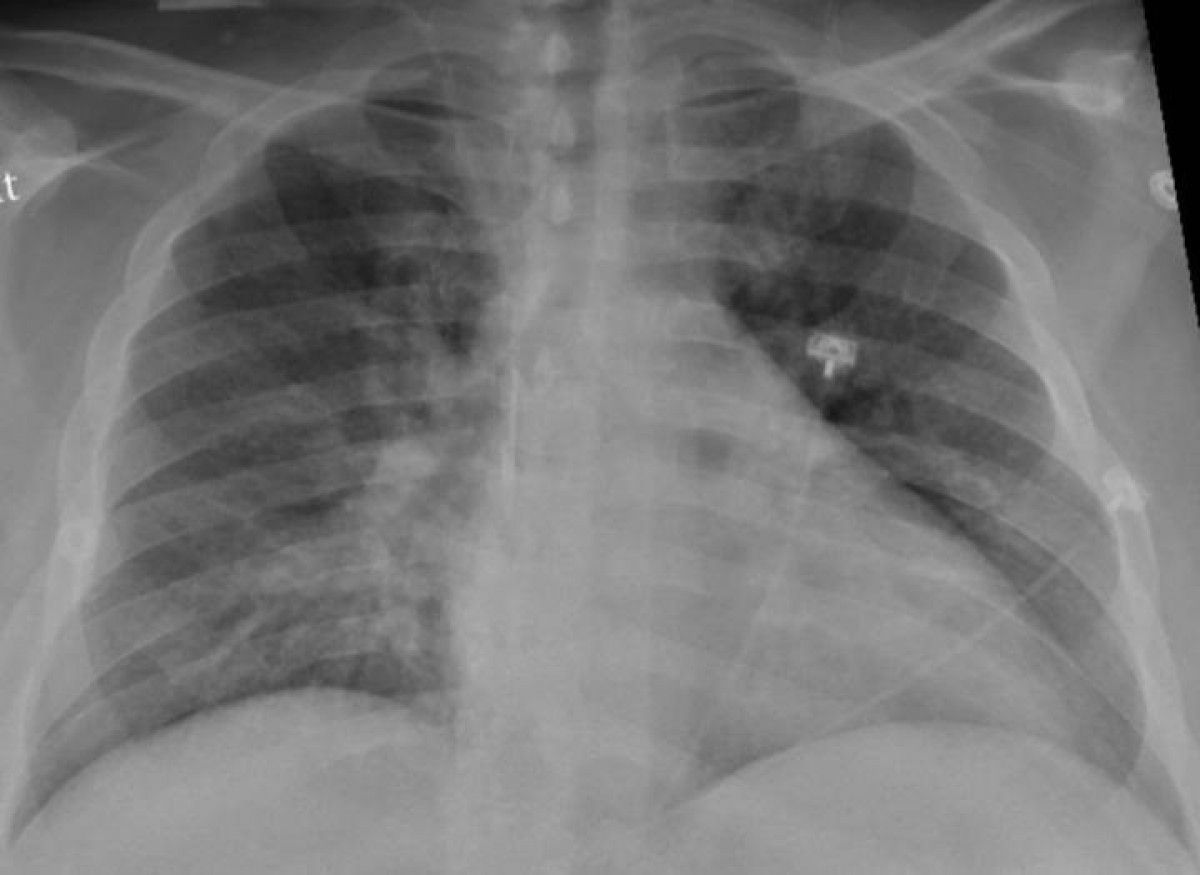

Archivo - La radiografía de tórax de un paciente positivo de COVID-19 que muestra una neumonía en la parte inferior de los pulmones.

Radiografía del tórax @ep